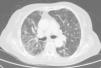

Caso clínicoSe trata de una mujer de 83 años, con antecedentes de hipertensión arterial en tratamiento con amlodipino 5mg/día, enfermedad renal crónica en estadio iii, secundario a nefroangioesclerosis (filtrado glomerular de 45ml/min) y polimialgia reumática en tratamiento crónico con metotrexato 15mg/semanal, desde hace 4 años, aproximadamente. Durante los últimos años ha permanecido con buena estabilidad clínica y analítica, no requiriendo tratamiento corticoideo asociado ni ajustes de su medicación habitual. Seis semanas previas al ingreso presentó de forma progresiva astenia, disnea, tos productiva y pérdida ponderal de 5 kg durante este tiempo. No fiebre termometrada, no artralgias ni debilidad muscular. En el ingreso, se objetivó disnea en reposo con saturación de oxigeno basal del 90%, auscultación pulmonar con crepitantes finos bilaterales, no adenomegalias ni visceromegalias palpables, elevación de la velocidad de sedimentación globular de 69mm, proteína C reactiva de 3,5mg/dl y radiografía de tórax, donde destacó un infiltrado reticular bilateral difuso y asimétrico con afectación periférica, más acentuado en las bases y en el lóbulo superior derecho (fig. 1). Tras realizar un diagnóstico diferencial de neumopatía subaguda en el contexto de la paciente, la sospecha de neumopatía por metotrexato fue el principal planteamiento, por lo que se suspendió dicho tratamiento, se inició corticoterapia por vía intravenosa de 48mg/día de metilprednisolona y medidas de soporte, a pesar de lo cual no se objetivó clara mejoría. Se realizó una tomografía axial computarizada de alta resolución (TACAR) torácico, objetivándose un engrosamiento intersticial parcheado de predominio periférico y en las bases pulmonares, así como pequeñas adenopatías mediastínicas inespecíficas (fig. 2). Las pruebas de función respiratoria mostraron una espirometría forzada con valores en el límite bajo de la normalidad, con una capacidad vital forzada (FVC) de 1.340ml (82%), un volumen de flujo espiratorio en el primer segundo (FEV1) de 1.130ml (88%) y el cociente FEV1/FVC del 84%, asociado a un descenso grave de la difusión pulmonar de monóxido de carbono (DLCO) del 33% y corregido según el volumen alveolar (KCO) del 54%. En el resto de las pruebas complementarias, no se evidenciaron alteraciones en el hemograma, la serología para gérmenes atípicos, el estudio de marcadores tumorales, los hemocultivos, el estudio seriado de esputo ni en el Mantoux/Booster, por lo que se realizó una broncoscopia con estudio del lavado broncoalveolar (LBA) y broncoaspirado, obteniéndose resultado positivo en la reacción en cadena de la polimerasa (PCR) para CMV asociado a un incremento del índice de linfocitos CD4/CD8 de 3.47, con el resto de estudio para gérmenes comunes, tuberculosis, Pneumocistis jiroveci y hongos negativo. Se amplió el estudio microbiológico detectándose IgG para CMV (+), IgM para CMV (–) y carga viral CMV en plasma (+), por lo que se inició tratamiento por vía intravenoso, ajustado según función renal, con ganciclovir 300mg/12 h durante 14 días, cambiando posteriormente a valganciclovir 900mg/12 h por vía oral durante 14 días, con buena tolerancia a la medicación y respuesta clínica, mejorando los parámetros radiológicos, serológicos (carga viral CMV indetectable) y de función respiratoria (DLCO 57,52%, KCO 80,90%, FVC 1.950ml [119%] y FEV1 de 1.680ml [130%]).